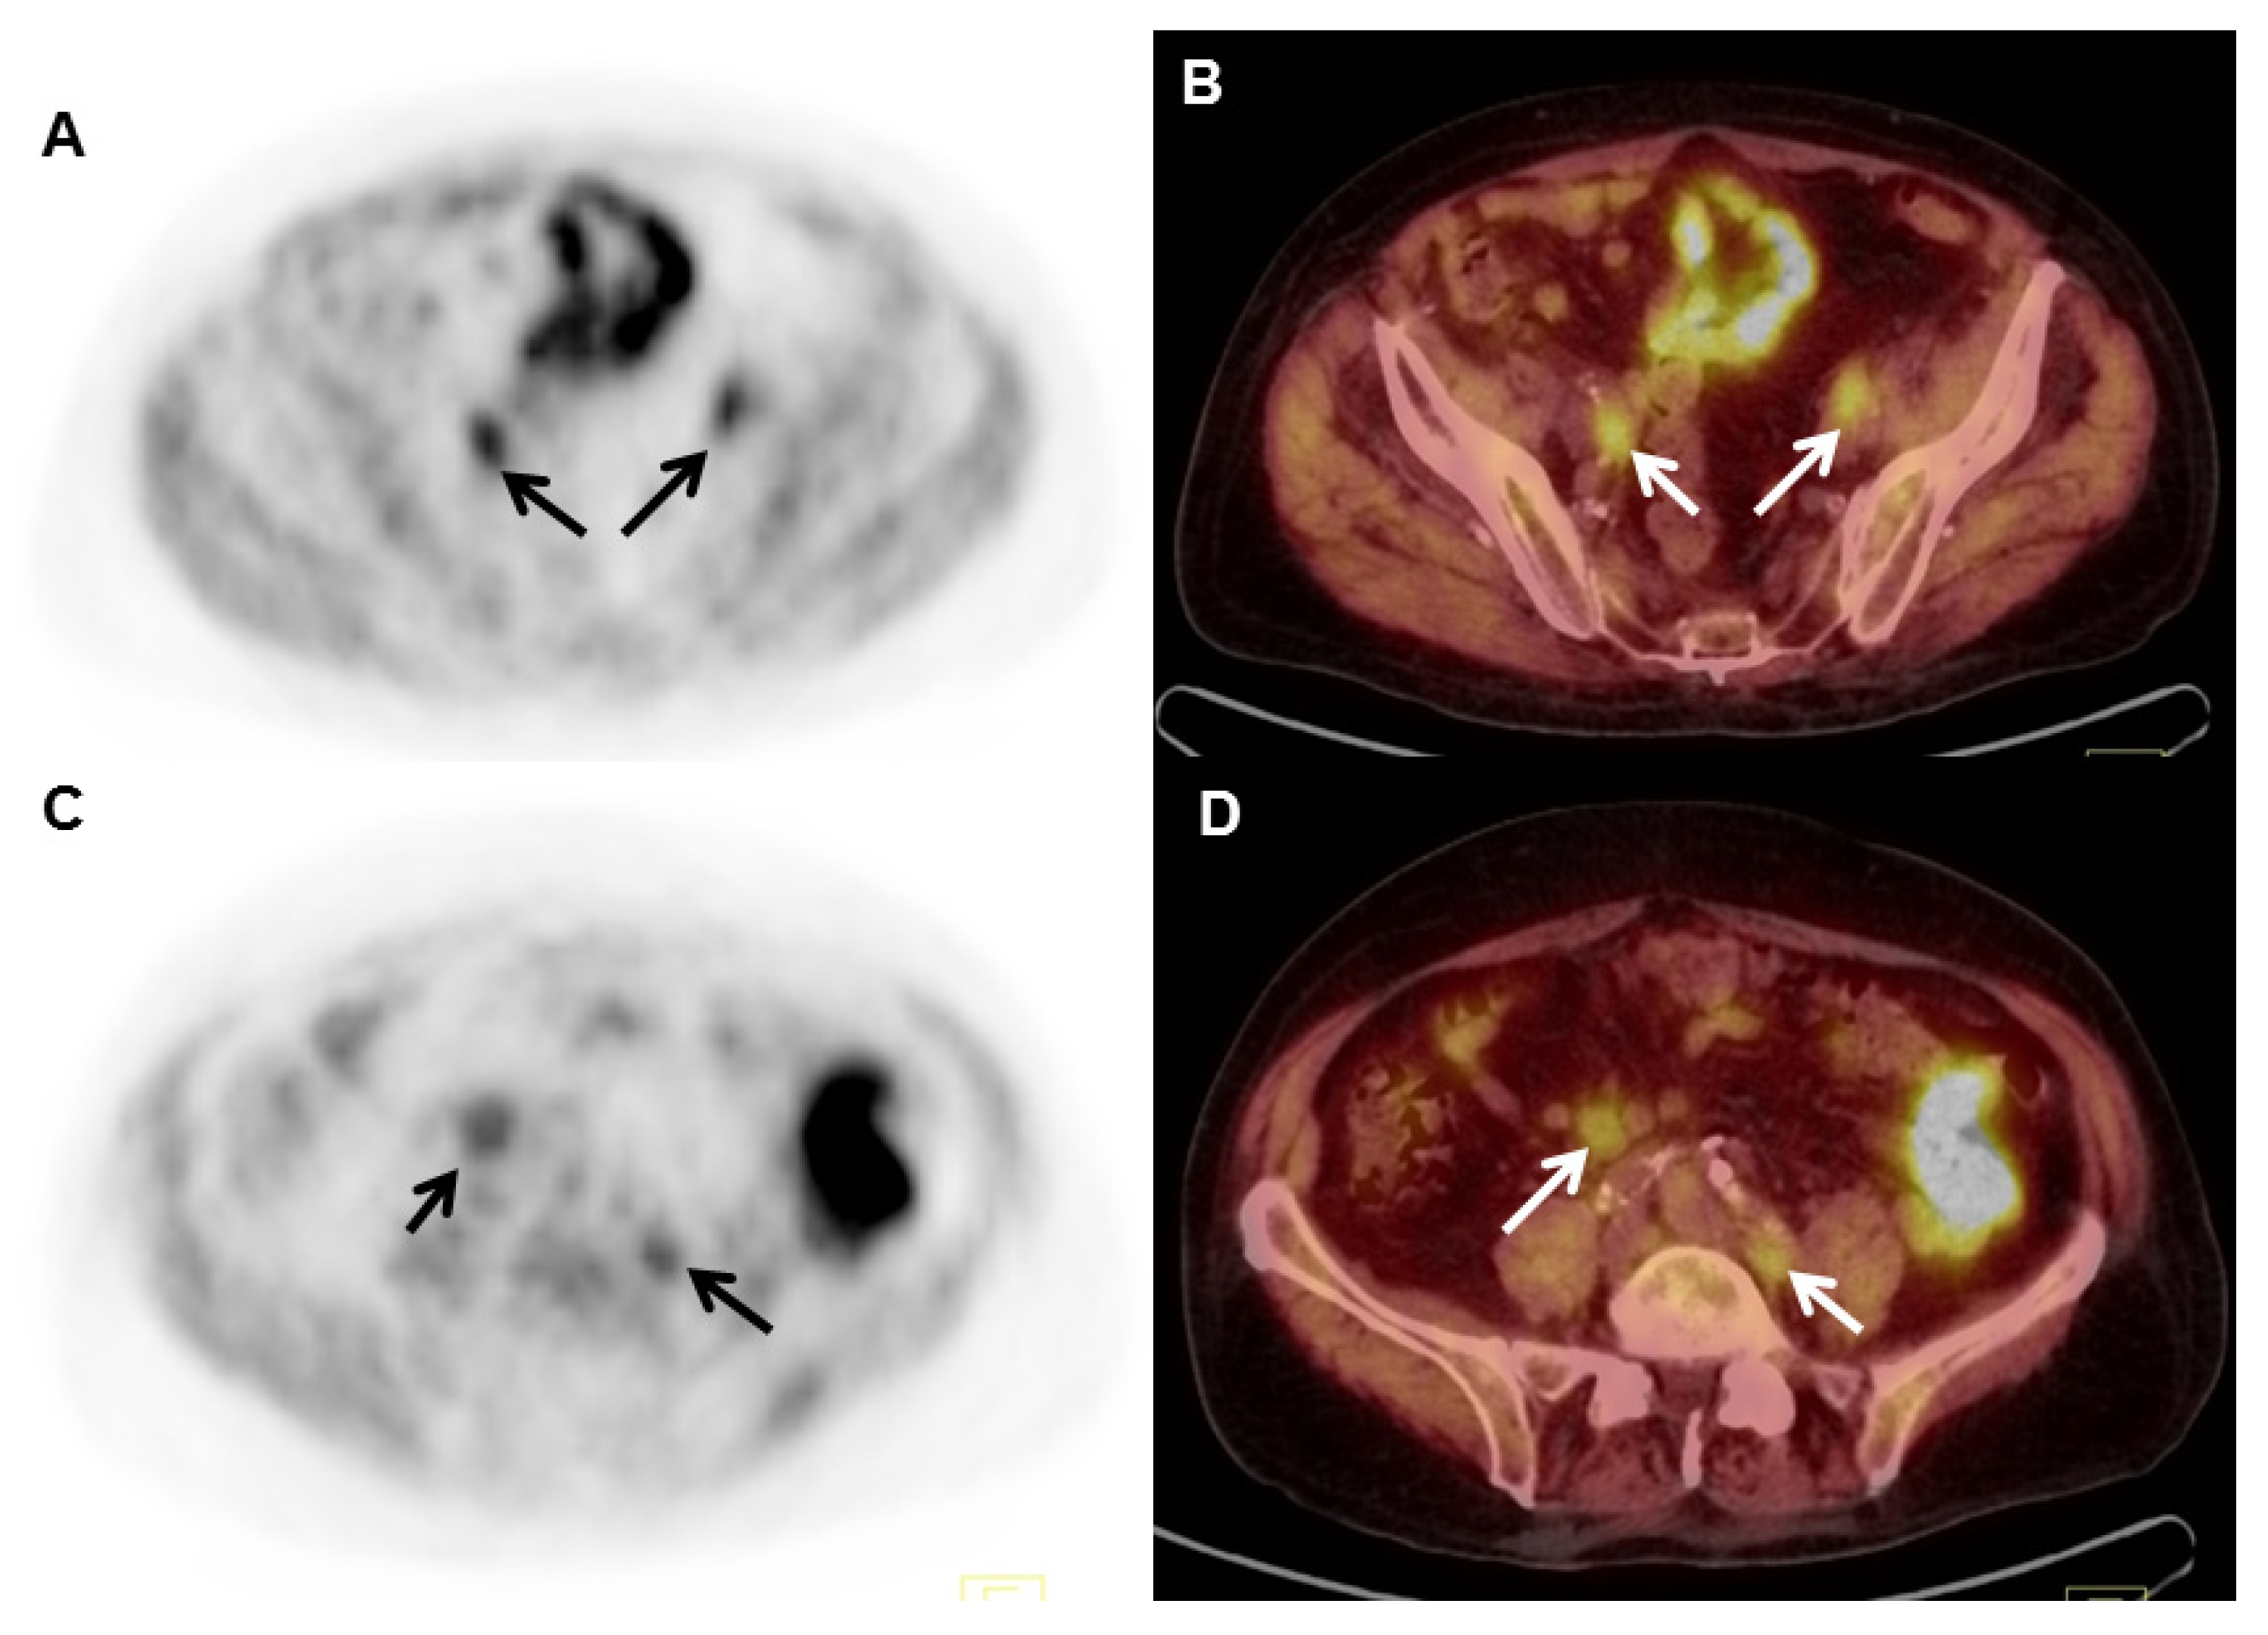

- Gusman, M.; Aminsharifi, J.A.; Peacock, J.G.; Anderson, S.B.; Clemenshaw, M.N.; Banks, K.P. Review of 18F-Fluciclovine PET for Detection of Recurrent Prostate Cancer. Radiographics 2019, 39, 822–841. [Google Scholar] [CrossRef]

- Savir-Baruch, B.; Odewole, O.; Alaei Taleghani, P.; Master, V.; Nieh, P.; Halkar, R.; Jani, A.; Goodman, M.; Yu, W.; Schster, D. Anti-3-[F18] FACBC uptake pattern in the prostate affects positive predictive value and is associated with the presence of brachytherapy seeds. J. Nucl. Med. 2013, 54, 346. [Google Scholar]